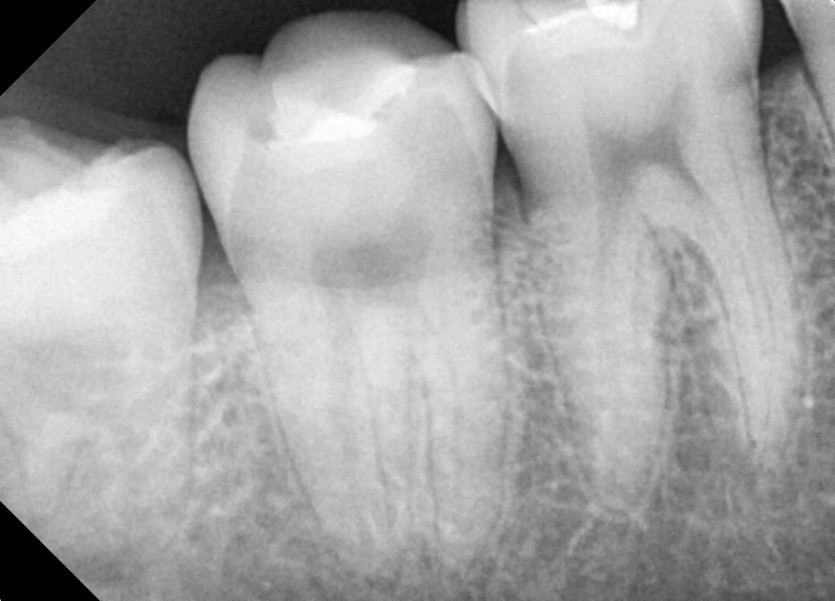

#48 사랑니 발치

구강 외과 전문의가 당일 발치했습니다.